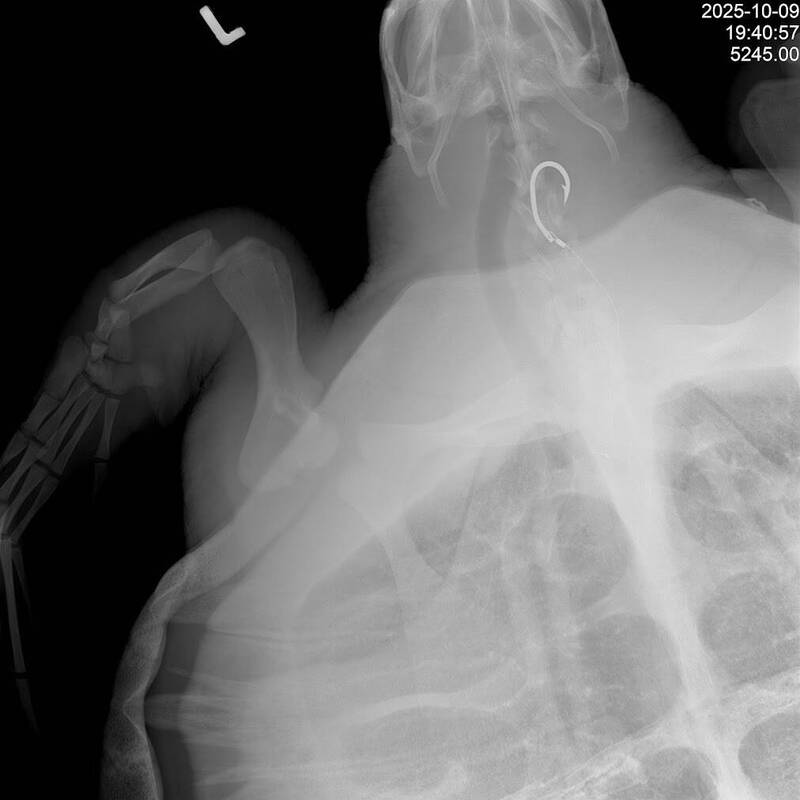

卡魚網又吞鉤!垂危「小欖」康復重返大海 屏東後灣野放

喜訊!一隻在鬼門關前走一遭的保育類欖蠵龜,在國立海洋生物博物館(海生館)的悉心照護下康復出院,重返浩瀚大海,這場充滿希望的野放活動選在屏東後灣沙灘舉行,海生館16日特別攜手牡丹...…